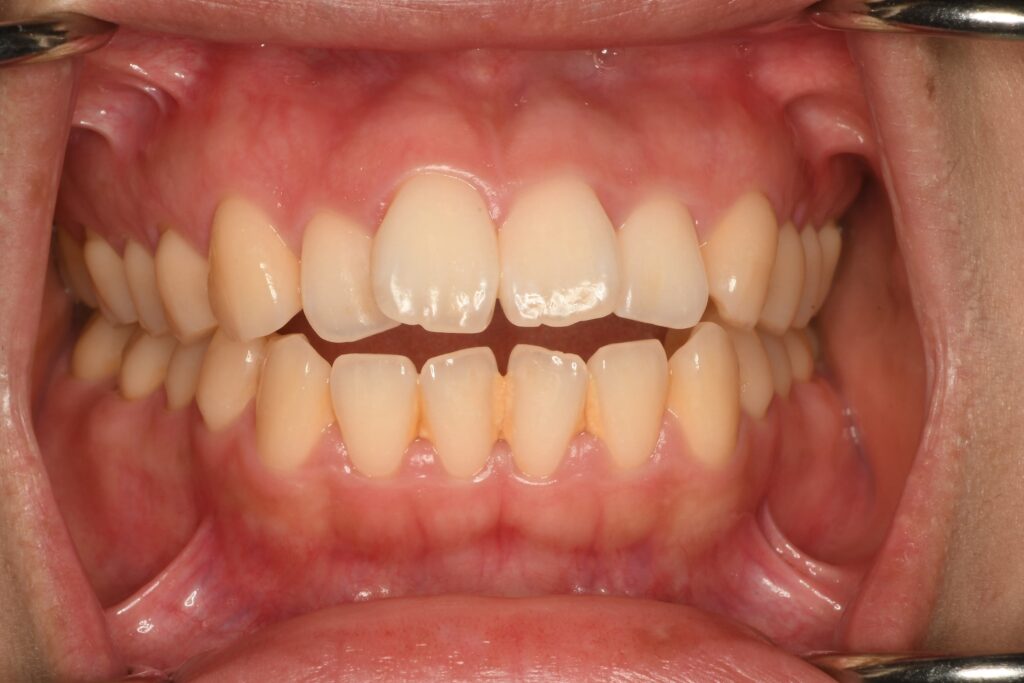

写真を見てもらっても分かる通り、前歯が噛んでいません。正しい表現をさせてもらうと、前歯は噛んでいるわけではありません。下の前歯に上の前歯が被さるような位置関係になるのが正常です。今回のようなケースは気にしたいのが奥歯の位置関係です。。これをハッキリさせる為には精密検査が必要です。